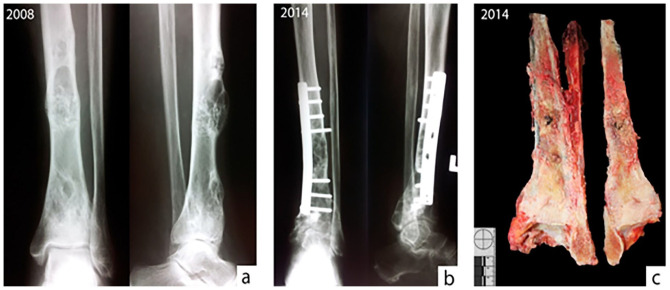

Adamantinoma (AD) is a rare, slow-growing primary malignant bone tumor characterized by a biphasic morphology of clusters of epithelial cells and spindle cell osteofibrous components. A strong relationship between AD and osteofibrous dysplasia (OFD) has been proposed, while fibrous dysplasia (FD) has been rarely associated with AD. We present an AD case that was followed and histologically evaluated 3 times over 6 years with different morphological patterns. The tumor in the primary biopsy and after complete resection showed classical features of AD and osteofibrous-like pattern, while the recurrent lesion presented with exclusively spindle cell morphology and was thus diagnosed as FD. However, the extensive immunohistochemical analysis in all 3 lesions revealed strong reactivity for pancytokeratin, vimentin, p63, and podoplanin, which are characteristic for AD. Although, in the FD-like section of the tumor from the first recurrence the positivity of podoplanin was stronger than pancitokeratin, which was variably positive on spindle cells. The present case highlights the problem of diagnosing AD based on a single biopsy with one tumor's component predominating over the other, and at the same time emphasizes the importance of using immunohistochemical staining for keratin and podoplanin when the histopathological features of (osteo)fibrous lesion can be linked to AD.